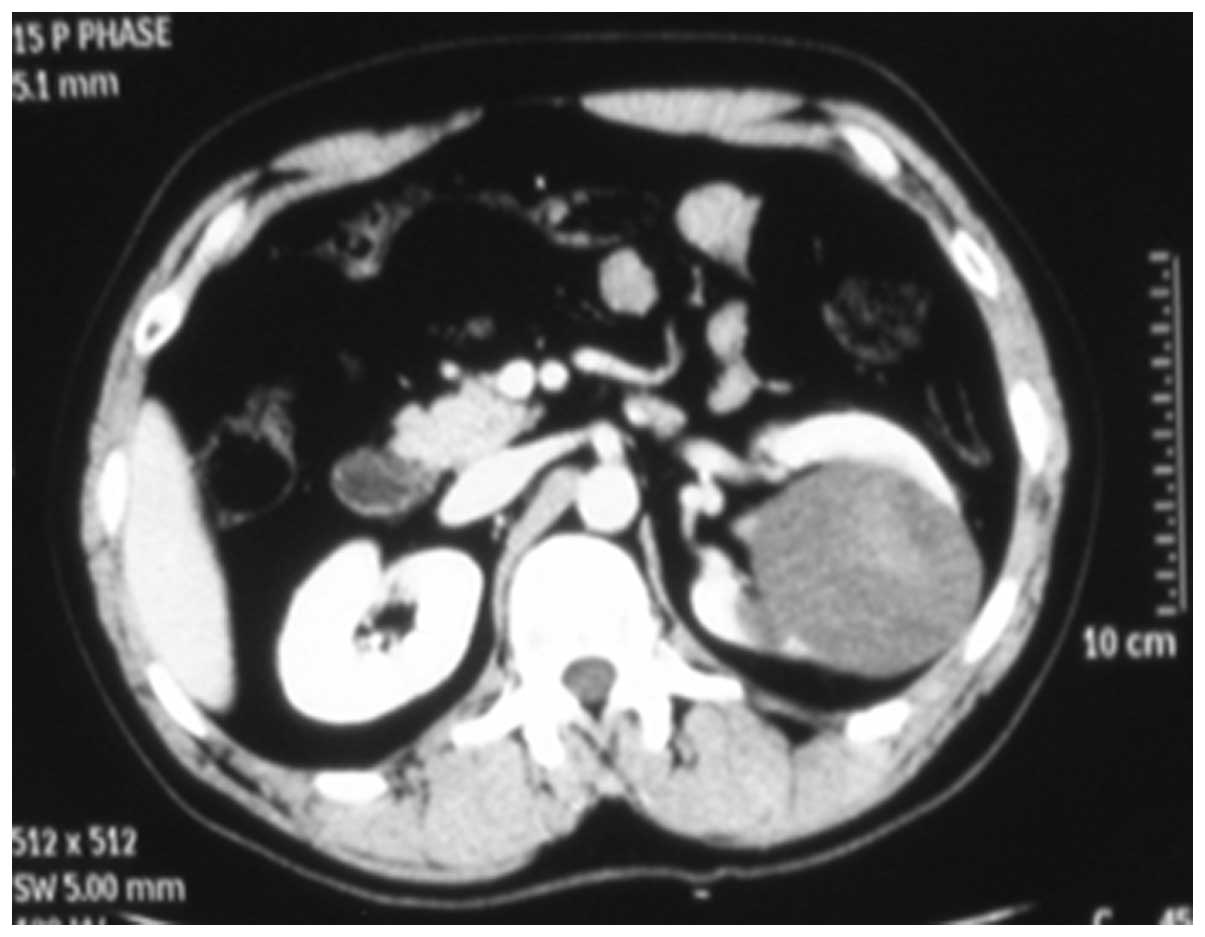

Clinical characteristics and pathology of thyroid‑like follicular carcinoma of the kidney: Report of 3 cases and a literature review

Thyroid‑like follicular carcinoma (TLFC) of the kidney is an extremely rare type of renal tumor, which has not been classified under a known subtype of renal cell carcinoma. It is histologically similar to the primary thyroid follicular carcinoma; however, the characteristics lack thyroid immunohistochemical markers. The aim of the present study was to illustrate the clinical characteristics of 3 new cases along with a review of the literature. The patients were compared with regards to gender, age, location and size of the tumor, imageology, morphology, immunohistochemistry and prognosis. According to the limited data, TLFC occurs mainly in young women and its clinical manifestations have no difference with other renal tumors. Its imageological features resemble a large spectrum of benign and malignant renal and extra‑renal conditions, which should be eliminated in the diagnostic process. Confirmed diagnosis depends on the examination of pathology and immunohistochemistry. Surgical ablation is the preferred therapeutic method. Currently, TLFC has a relatively good prognosis; however, this conclusion requires further cases and long‑term follow‑ups. Improving the understanding of TLFC can help avoid misdiagnosis and prevent inappropriate treatment.

Figure 3